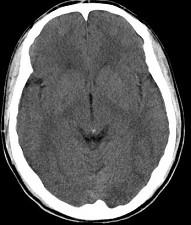

问题 男,23岁,近3天感到头痛、头晕,乏力,精神焦虑,CT检查如图所示,最可能的诊断为()

选项 A.脑萎缩 B.脑室出血 C.正常颅脑 D.脑水肿 E.胶质瘤

答案 C